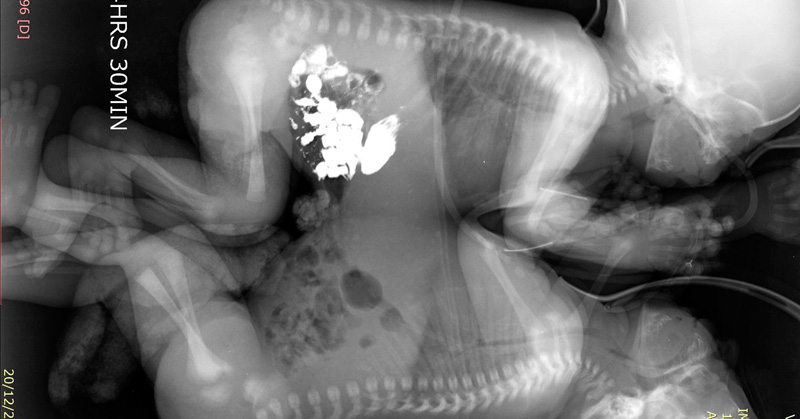

Separan con éxito a siameses en Guanajuato

Los pequeños nacieron vía cesárea el 15 de diciembre de 2017, pesaron poco más de cinco kilogramos y midieron 45 centímetros